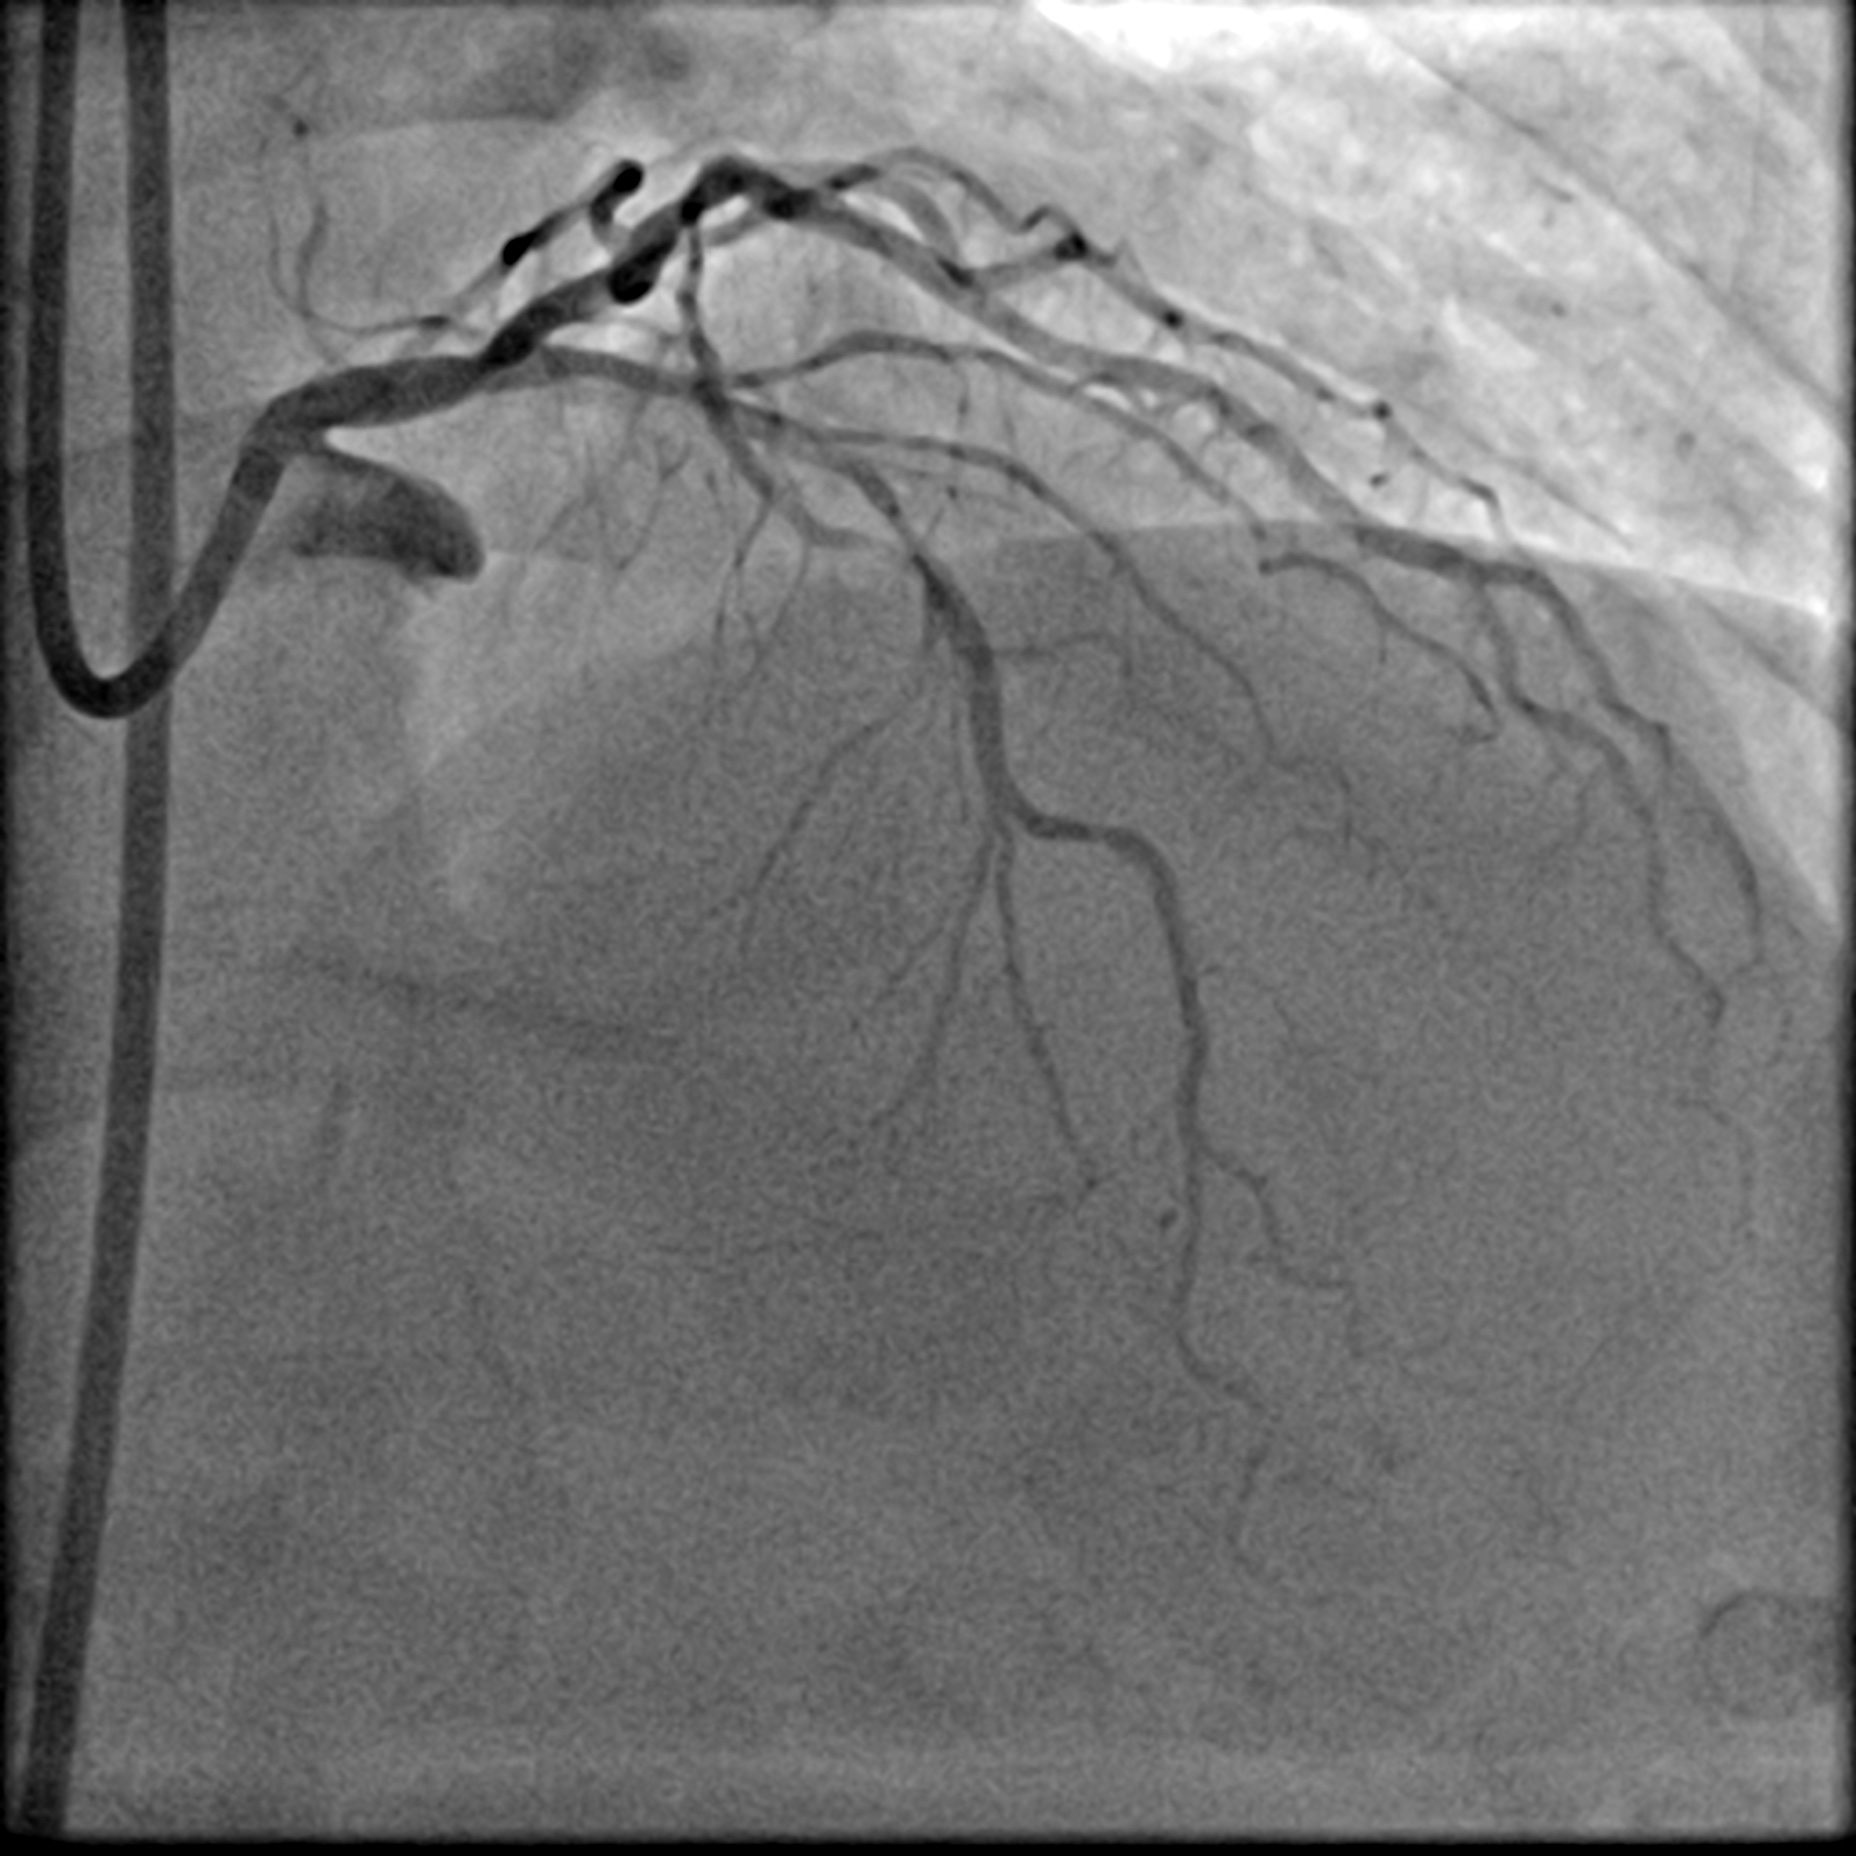

Relevant Catheterization Findings

Coronary angiogram showed a Left Main Stem (LMS) bifurcation lesion (Medina 0,1,1) with visible calcification in the proximal left anterior descending artery (LAD). IVUS confirmed severe calcification in the proximal LAD and a calcified nodule causing significant occlusion at the left circumflex artery (LCx) ostium. The right coronary artery (RCA) was spared. Due to severe calcification, a calcium debulking device was required, and the decision was made to proceed with Orbital Atherectomy (OAS).